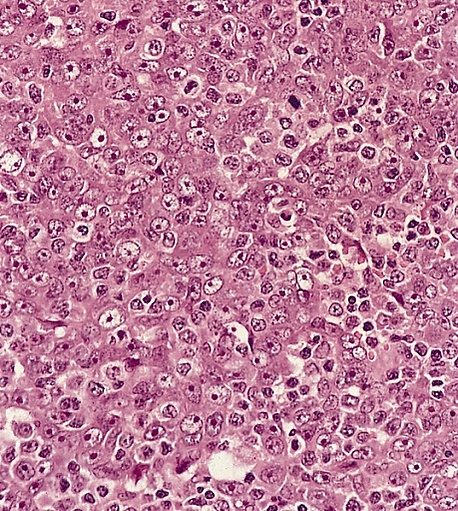

- неороговевающий рак, недифференцированный подтип: характеризуется либо синцитиальным расположением клеток с нечёткими границами, либо диффузным инфильтратом из не связанных между собой клеток, напоминающим неходжкинскую лимфому. Опухолевые клетки имеют умеренно эозинофильную или амфофильную цитоплазму, округлые ядра, крупные эозинофильные ядрышки и везикулярный хроматин. Значимого ороговения не наблюдается. Практически всегда присутствуют апоптоз и высокая митотическая активность. Обычно, хотя и не всегда, опухоль сопровождается выраженным неопухолевым лимфоплазмоцитарным инфильтратом. Некроз встречается редко;